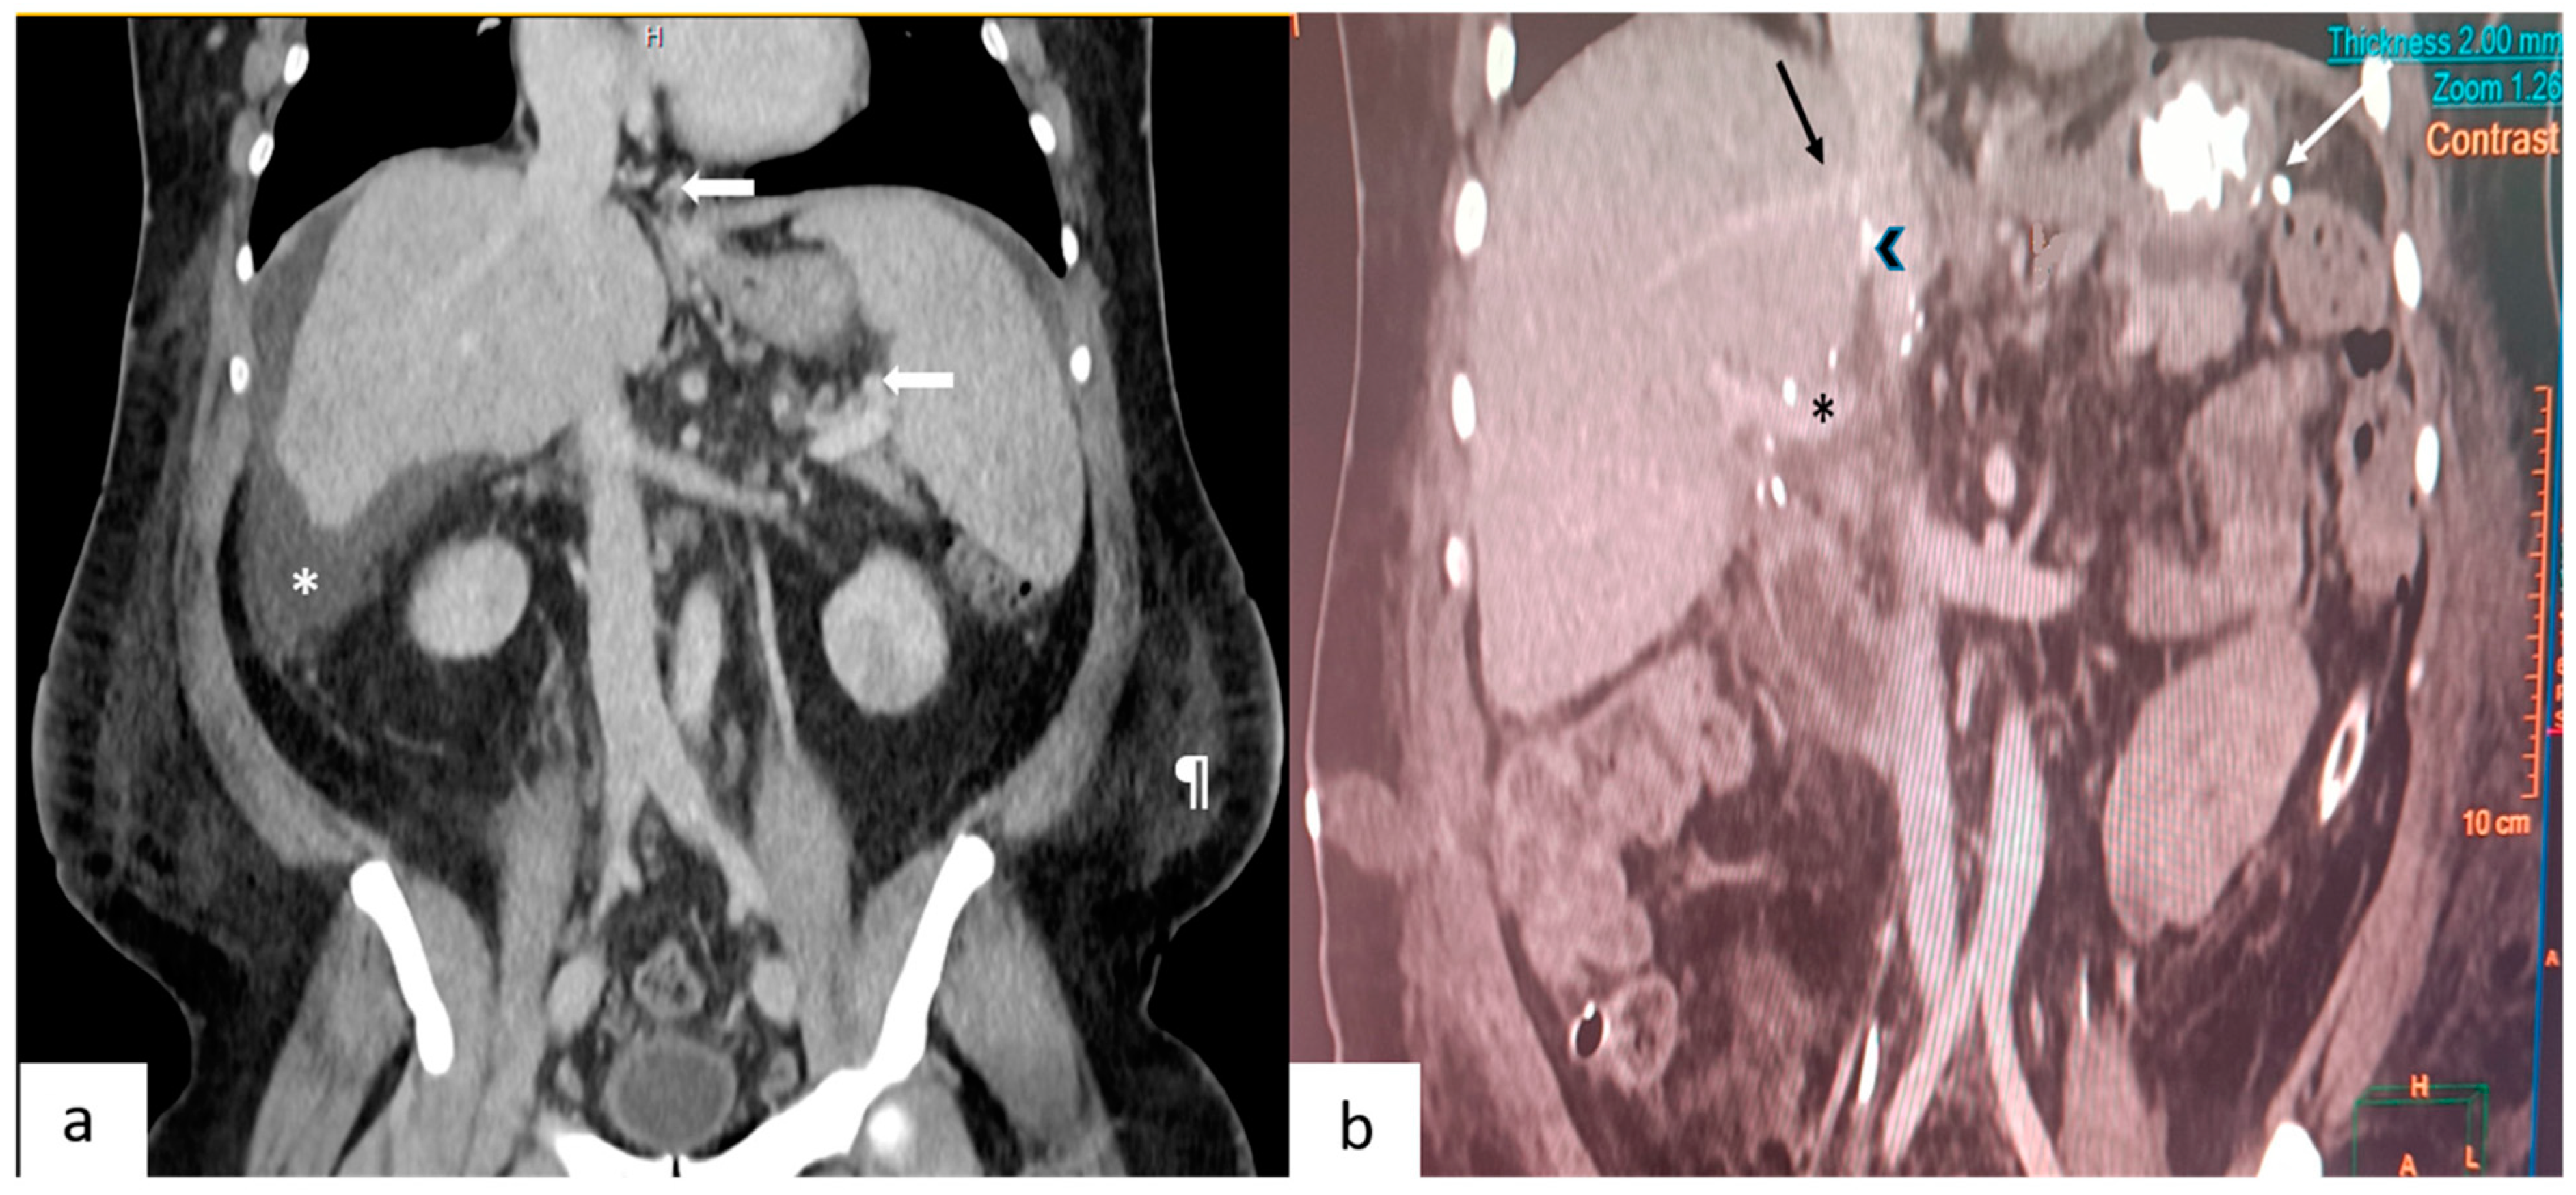

Figure 1.

(a) This depicts a coronal section of a pre-operative contrast-enhanced CT scan. Arrows point to the gastroesophageal and splenic perihilar collaterals. Also seen are ascites (*) and the prominent subcutaneous fat (¶) in the flanks. (b) This depicts a coronal section of a post-operative CT scan performed on day 7. Seen are the junction of the right hepatic vein (black arrow), polytetrafluroethylene graft (arrowhead) with the inferior vena cava, portal vein (*) and vascular staplers (white arrow) used during splenectomy.

It is interesting to analyze how a very small graft (GRWR 0.49) worked for the patient without any features of SFSS. Firstly, the donor liver was of excellent quality. It was a 26-year-old liver without any trace of fat infiltration (not biopsiedtherefore). Secondly, the outflow was reconstructed meticulously in a standard manner [6]. Doppler waveforms of the common right with reconstructed anterior sector outflow and the inferior hepatic vein were triphasic. Figure 1b depicts a section of the post-operative CT scan. Thirdly the GRWR may have been spuriously low due to the fluid overload of the recipient. An accurate weight of the recipient is difficult to determine in the presence of cirrhosis and ascites, but some of the indicators of falsely high weight are tense ascites, fluid overload, anasarca, and renal dysfunction with oliguria. If possible, the patient should be offloaded as much as possible. The index patient was diuretic intolerant, and therefore we decided to proceed with the transplant after the creatinine normalized (peak value 1.8 mg/dL). Post-transplant, his weight reduced to 90 kg within a period of one month. Notwithstanding this, the GRWR for a 550 g liver in a 90 kg recipient is still low (0.61), and therefore making a pre-operative decision to proceed in this situation is certainly a difficult one to make. Fourthly, a second hit to a regenerating small graft might tilt the scales unfavorably. Immunosuppression should be carefully optimized to prevent rejection. This patient had a bile leak that was detected towards the end of the first week. This was picked up on a CT scan performed on a high index of suspicion as it was a ‘high risk’ biliary anastomosis. There were two anastomoses and the recipient cystic duct was anastomosed to the donor’s right posterior duct. As the bile leak occurred when the graft function had already been stabilized, it did not significantly impair patient recovery. It was managed as a controlled external biliary fistula followed by endoscopic biliary stenting after 5 weeks.